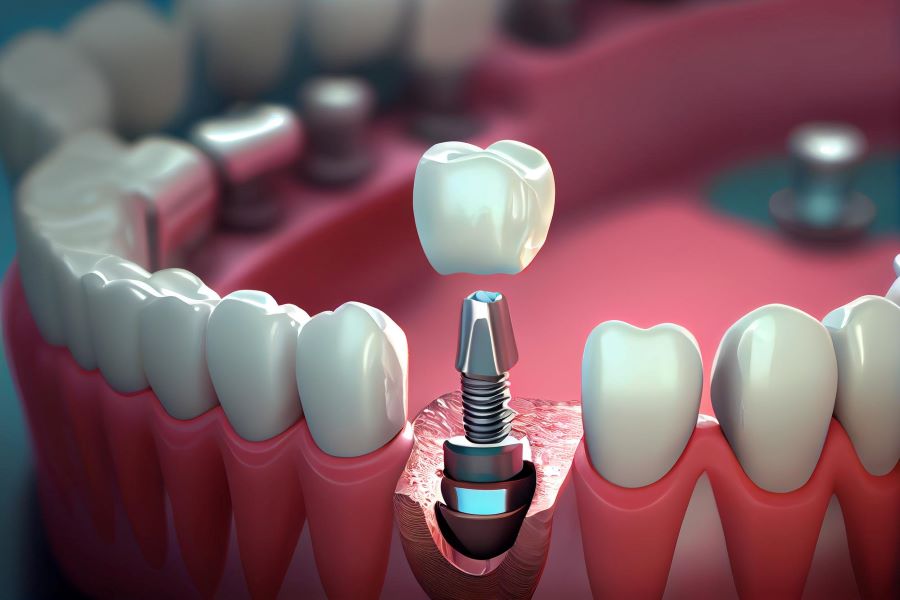

جوش خوردن را میتوان اصلیترین مرحله پس از کاشت ایمپلنت دانست. در این روند ایمپلنت با فک شما اتصال مناسبی برقرار میکند و ساختاری ویژه بین این دو قطعه ایجاد میشود. این پیوند منجر به استحکام بیشتر ایمپلنتهای شما خواهد شد.

مدت زمان جوش خوردن ایمپلنت

به طور کلی نمیتوان مدت زمان مشخصی را برای این امر عنوان کرد. شرایط کاشت ایمپلنت در هر شخصی متفاوت است و همین امر منجر به متغیر بودن بازه زمانی مورد نیاز برای جوش خوردن کامل ایمپلنت میشود. در هر صورت حداقل سی روز طول میکشد تا ایمپلنتها به صورت مناسب جوش بخورند. دکتر وزیری در این رابطه می فرماید:

به هر حال طبق تحقیقات و بررسی های به عمل آمده از نتایج کاشت ایمپلنت های دندانی مشخص شده که جوش خوردن ایمپلنت دندان فک بالا سه ماه و فک پایین پنج ماه به طول می انجامد.

پیشگیری همیشه بهتر از درمان است و این مورد در مورد موضوع عدم جوش خوردن ایمپلنت نیز صدق میکند. به جای اینکه خود را درگیر راهکارهای مختلف مربوط به حل این موضوع کنید، بهتر است از همان ابتدا کاشت ایمپلنت خود را به مراکز معتبر دندانپزشکی بسپارید.